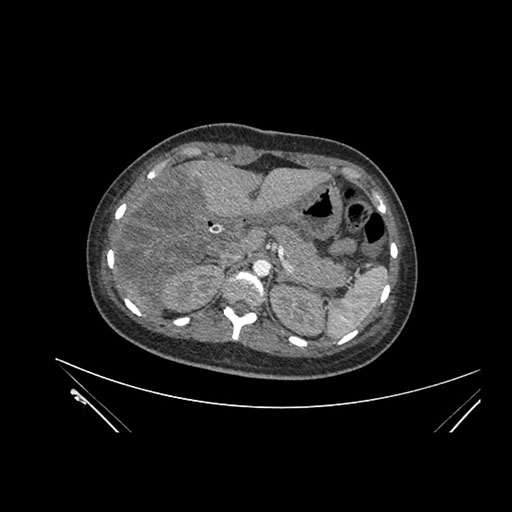

Imaging Analysis

Look through the patient's CT scan to identify any areas of concern for the necessary procedure.

Axial Venous

Based on initial findings, which issue(s) would you be most concerned about?